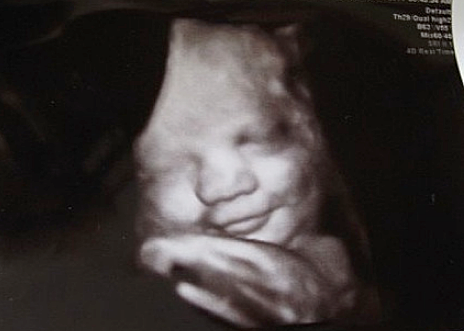

• Semana 25

Semana 25

Ya el bebe en esta semana ya le mide la columna 21cm hasta la cabeza ,pesa 700 gramos y puede sonreír, bostezar y su lengua ya puede salir de su boca.